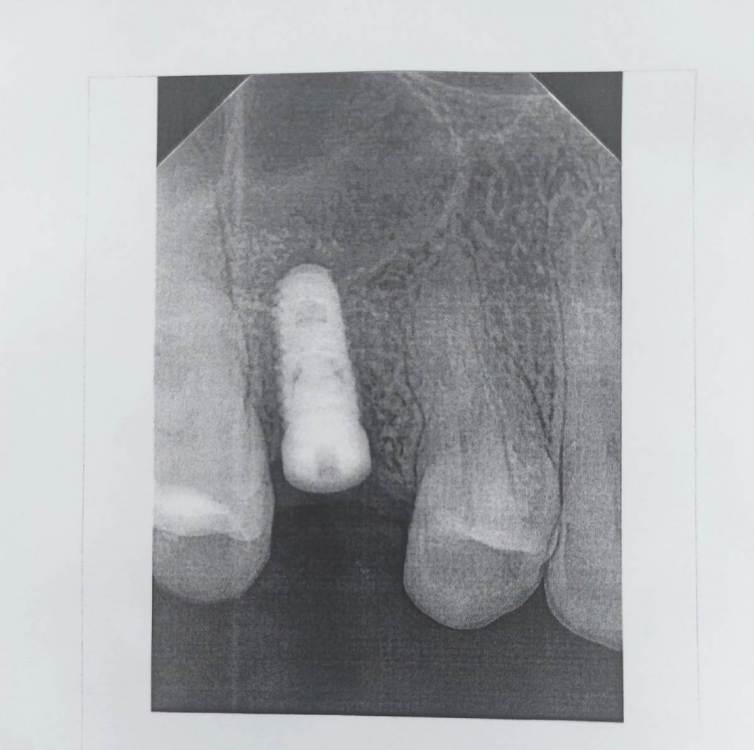

Gostya Опубликовано 18 февраля, 2023 Поделиться Опубликовано 18 февраля, 2023 (изменено) Установлен имплант с закрытым синус лифтингом. Начался гайморит, заключение кт снимка перфорация гайморовой пазухи 2 мм. Что делать с имплантом, удалять его? Не будет ли имплант в будущем постоянной причиной вновь повторяющегося гайморита, если не удалять? Изменено 18 февраля, 2023 пользователем Gostya Ссылка на комментарий

Irouil Опубликовано 18 февраля, 2023 Поделиться Опубликовано 18 февраля, 2023 (изменено) На снимке чётко видна бикортикальная фиксация импланта, что является вариантом нормы (а по мнению очень большого количества хирургов - оптимальным вариантом) его установки. В моей личной практике сотен установленных подобным образом имплантов, осложнений в виде гайморита не возникало ни разу, поэтому я считаю, что вероятность вины непосредственно имплантации в возникновении гайморита близка к нулю. Чтобы говорить что-то конкретное о гайморите надо а) быть ЛОР врачом и б) иметь на руках как минимум КТ головы, но , зачастую использование обычных сосудосуживающих средств в комбинации с гипертоническими аэрозолями позволяет устранить симптоматику острого гайморита и не дать ему перетечь в хронический. Изменено 18 февраля, 2023 пользователем Irouil 1 Ссылка на комментарий

Gostya Опубликовано 22 февраля, 2023 Автор Поделиться Опубликовано 22 февраля, 2023 Уважаемые доктора был установлен имплант с закрытым синус лифтингом. Кт снимок заключение пролабирование гайморовой пазухи в просвет 2мм. Лором поставлен диагноз гайморит. Сейчас присутствует подвижность импланта при осмотре. Сделан прицельный снимок. Скажите что по этому снимку можете сказать? Периимплантит и удаление импланта ? Или что? Ссылка на комментарий

Irouil Опубликовано 22 февраля, 2023 Поделиться Опубликовано 22 февраля, 2023 Если присутствует подвижность импланта - его надо удалять. Но у Вас на импланте стоит формирователь десны, поэтому определить подвижность импланта можно только удалив формирователь. На очном осмотре, если действительно что-то подвижно, можно подкрутить формирователь до упора, если имплант неподвижен - на этом завершить, если подвижен - удалить. Рассуждения о деталях техники выполнения различных видов операций немного превышает компетенции этого форума. Ссылка на комментарий

annda Опубликовано 22 февраля, 2023 Поделиться Опубликовано 22 февраля, 2023 Приподнимают слизистую пазухи( это и есть лифтинг),а костную стенку этой самой пазухи пробивают специальным инструментом или пропиливают различными фрезами,кто как.За эту костную стенку затем фиксируют верхушку имплантата,это бикортикальная фиксация Внутрь пазухи могут и пару мм имплантата ввести,а могут и 5 мм ,все индивидуально,в зависимости от клинической ситуации. Ссылка на комментарий